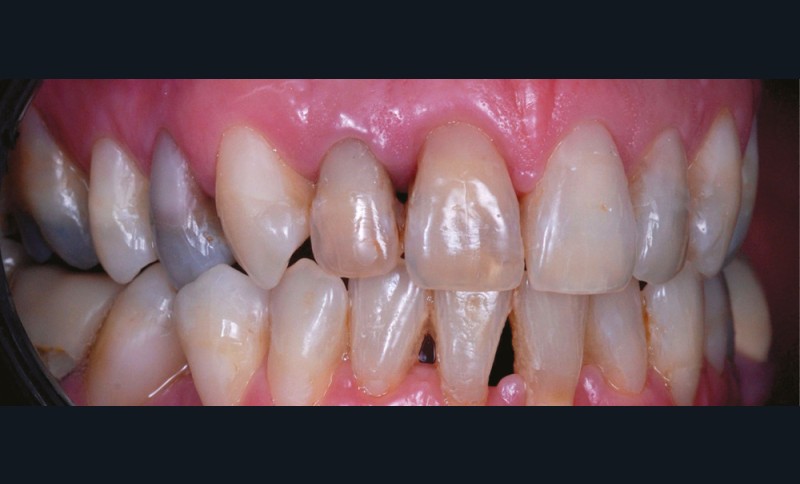

– les soins conservateurs et endodontiques [5] (fig. 4 et 5).

Les soins conservateurs et endodontiques sont majoritairement responsables des dyschromies des dents dépulpées. Nous allons développer ce point afin de mieux comprendre les paramètres régissant les colorations iatrogènes pour mieux les éviter et, si besoin, les corriger.

Les différents matériaux mis en contact avec la dent interagissent avec les tissus dentaires et provoquent des colorations.

Ainsi, les ciments d’obturation canalaire sont la cause principale des dyschromies de la dent dépulpée [6]. Les modifications de couleur peuvent apparaître après une semaine seulement, lorsqu’il s’agit de ciments oxyde de zinc/eugénol (ZoE) [7, 8] ou à un mois post-traitement dans le cas de certaines biocéramiques [6].

Parmi les agents responsables de cette dyschromie, on peut citer l’eugénol, contenu dans les ciments ZoE et l’oxyde de bismuth, utilisé comme radio-opacifiant dans certaines biocéramiques, et principalement le MTATM [9]. L’oxyde de bismuth, quelle que soit sa concentration, même modérée dans le cas du MTA WhiteTM, provoque une coloration iatrogène de la dent en quelques semaines seulement [10] (fig. 6) [10]. Afin d’éviter ce type de dyschromies en secteur esthétique, il s’agit donc de privilégier dans notre pratique des biocéramiques qui contiennent un autre radio-opacifiant tel que l’oxyde de zirconium qui, lui, ne va pas créer de coloration iatrogène (BiodentineTM, TotallfillTM ou le BioRootTM) [11].